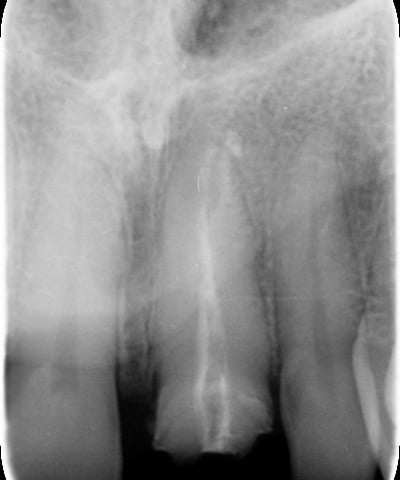

Trattamento endodontico inadeguato: il precedente trattamento canalare era insufficiente, lasciando il dente vulnerabile a infezioni e compromettendone la prognosi a lungo termine.

Trattamento Canalare Incongruo

Il primo step è stato il ritrattamento endodontico, essenziale per garantire la salute a lungo termine del dente. Dopo la rimozione della vecchia otturazione canalare, è stata effettuata una detersione accurata con irriganti specifici e successiva otturazione tridimensionale per prevenire recidive infettive.